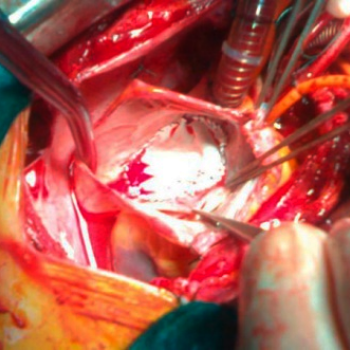

Centrum komplexní péče o vrozené srdeční vady v dospělosti vzniklo  v roce 2015  díky spolupráci  Centra kardiovaskulární a transplantační chirurgie s Interní kardiologickou klinikou Fakultní nemocnice  Brno a nabízí zcela komplexní péči o dospělé nemocné s vrozenou srdeční vadou. Portfolia jednotlivých pracovišť se navzájem doplňují.  Centrum poskytuje ambulantní sledování pacientů se všemi typy vrozených srdečních vad, neinvazivní a invazivní diagnostiku včetně transesofageální echokardiografie s využitím 3D zobrazení.  Centrum kardiovaskulární a transplantační chirurgie Brno provádí operace, reoperace a  intervenční výkony u vrozených srdečních vad a současně se věnuje chirurgické léčbě pokročilého srdečního selhání vč. implantace mechanických srdečních podpor a transplantace srdce ( Tým lékařů , seznam prováděných operačních a intervenčních výkonů).  V rámci Interní kardiologické kliniky FN Brno poskytuje invazivní  řešení arytmií ( radiofrekvenční ablace, kardiostimulace vč. resynchronizační léčby), některé intervence (uzávěry defektů septa síní) , organizaci nekardiálních operací a péči o gravidní včetně porodu probíhají v rámci Interní kardiologické kliniky FN Brno.   Návaznost na kardiologii dětského věku je zajištěna spoluprací s Fakultní dětskou nemocnicí v Brně.  Ambulantní péče probíhá na obou klinikách paralelně.